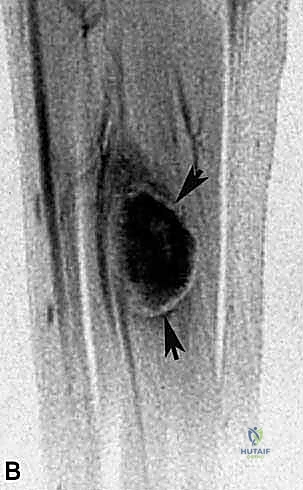

- التصوير بالرنين المغناطيسي (MRI) مع الصبغة:

هو المعيار الذهبي والأداة الأهم. يوفر الرنين المغناطيسي صورًا عالية الدقة للأنسجة الرخوة. يسمح للبروفيسور هطيف برؤية الحجم الدقيق للورم، وموقعه داخل عضلة النعل، ومدى قربه أو التصاقه بالعصب الظنبوبي والشريان المأبضي. الرنين المغناطيسي هو الخريطة التي يُبنى عليها التخطيط الجراحي. - التصوير المقطعي المحوسب (CT Scan) للصدر: